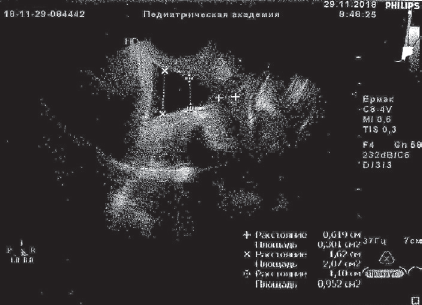

В анализах: общий белок крови 59 г/л, СОЭ 34 мм/ч, лейкоцитарный индекс интоксикации (ЛИИ) 2,6 усл. ед. (норма до 1,5), лейкоцитурия до 10 в поле зрения. Остальные анализы в норме. По данным УЗИ предполагаемая масса тела (МТ) плода 1403 г, плацента по передней стенке матки, 1-й степени зрелости, амниотический индекс 123 мм, шейка матки укорочена до 11 мм, цервикальный канал воронкообразно расширен на всем протяжении до 11–19 мм, выполнен до наружного зева плодным пузырем. Данные кардиотокографии и допплер-исследования кровотока в маточно-плацентарном пространстве в норме.

Получала сохраняющую беременность терапию с подключением трех сеансов мембранного плазмафереза (МПА) с возвратом гепаринкриомодифицированной аутоплазмы (при двух МПА по 200 мл), 12 сеансов ФК ультрафиолетовыми (№ 6) и лазерными (№ 6) лучами, без осложнений. После курса лечения анализы крови нормализовались, по данным УЗИ картина улучшилась, появилась сохранная часть шейки матки 6 мм, вероятно, за счет снижения внутриматочного давления в каудальном направлении. Пролабирования плодного пузыря за пределы наружного зева не визуализировалось в зеркалах и при УЗИ (рис. 1, 2).

Рис. 1. Данные ультразвукового исследования пациентки Ч., 30 недель беременности, до курса эфферентной терапии

Fig. 1. Ultrasonic examination of patient Ch., 30 weeks of gestation, before efferent therapy

Рис. 2. Данные ультразвукового исследования пациентки Ч., 33 недели беременности, после курса эфферентной терапии, динамика положительная

Fig. 2. Ultrasonic examination of patient Ch., 33 weeks of gestation, after efferent therapy course — positive results